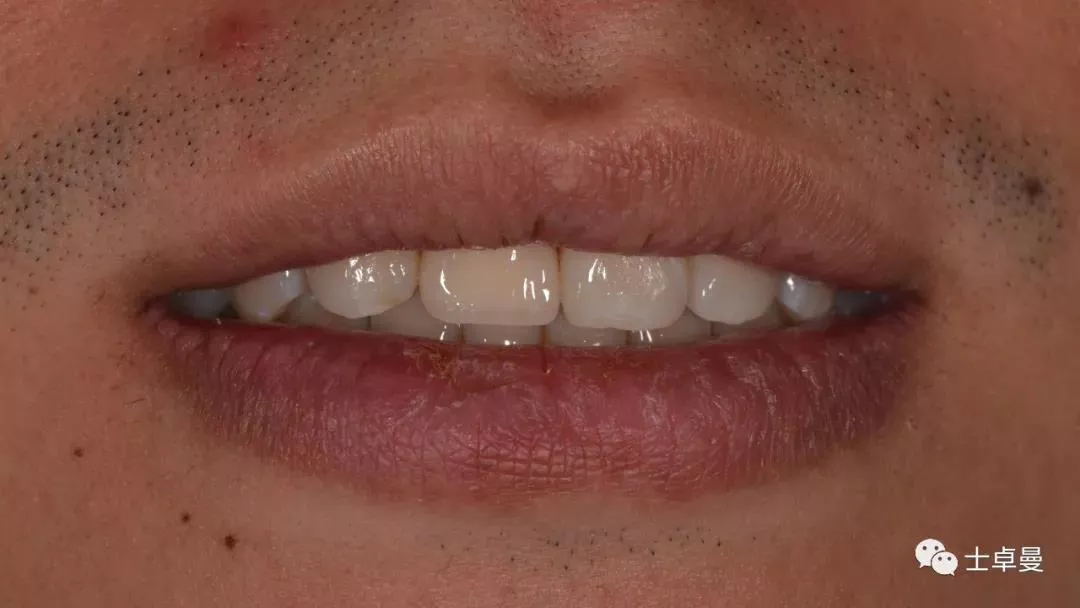

完成永久修复,骨弓轮廓、龈缘及龈乳头形态自然,可见牙龈点彩,修复体外形及色泽可,患者满意。